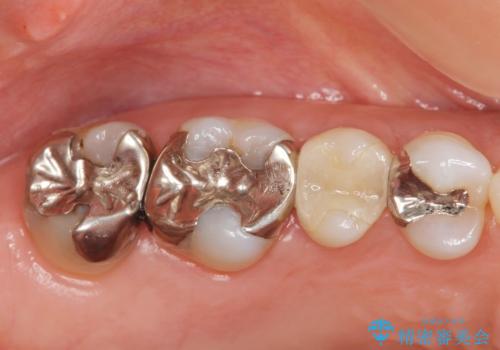

- フロスをしたときにひっかかりのある銀歯の修復を希望され来院されました。

銀歯の下には虫歯の再発が見られましたが、丁寧に除去を行いゴールドインレーによる修復を行いました。